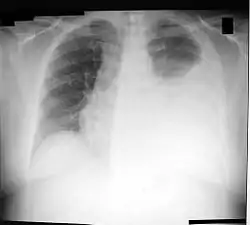

Торакоцентез (син. пункція плевральної порожнини, плевральна пункція) (з грец. Thōrax + kentesis = груди + проколювання) — медична маніпуляція, що застосовується для вилучення рідини з діагностичною або лікувальною метою з плевральної порожнини.